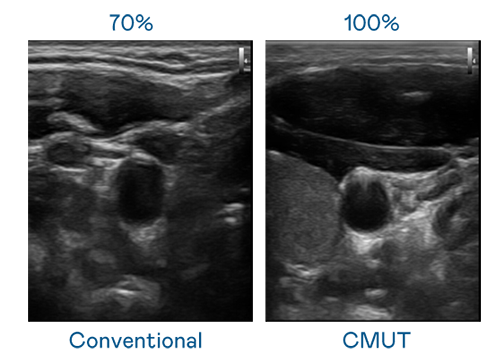

CMUT 技术是一种用电容式微机电元件来产生超音波讯号的技术。与传统 PZT 压电式技术相比,CMUT 频宽增加 30%,更宽频的超音波讯号让影像解析度大幅提升,是实现高影像品质医疗超音波扫描、促进精准医疗发展的关键技术。

大频宽带来超清晰影像

超音波影像的解析度高低,首先取决于探头能发出的讯号频宽。大庄家 CMUT 可提供高清晰的超音波讯号,提供高频宽、高灵敏度、影像纹理细节更高的超音波影像,协助医护人员缩短影像判读时间及利用精准的医疗影像进行诊断。